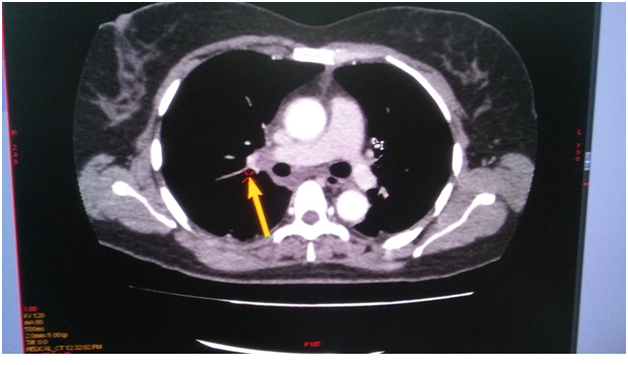

On the next day, at the day time, she felt progressive dyspnea. She was transferred to the intensive care department, where the suggestion of acute lung artery thromboembolic was taken, taken into account the character of dyspnea and extremely low level of blood saturation 60%, with weak response to oxygen therapy. The suggestion was approved by the chest tomography, where the thrombosis of both central lung arteries was revealed (Figure 1-4). After the short discussion among the colleagues, the procedure of thrombolysis was performed. We considered the extremely bad condition of the patient, weak response to oxygen therapy, young age and a kind of the operation. There were no pass to any cavity, no anastomosis, the inserted drainage system, to let blood flow out. Additionally, we had blood cell-save machine “Haemonetics Cell Saver 5+” (USA) to reinfuse blood and decrease blood loss.

Figure 1 (CT of thromboembolism in the left LA).

Figure 2 (CT of thromboembolism in the right LA).

Figure 3 (CT of thromboembolism in the left LA).

Figure 4 (CT of thromboembolism in the right LA).